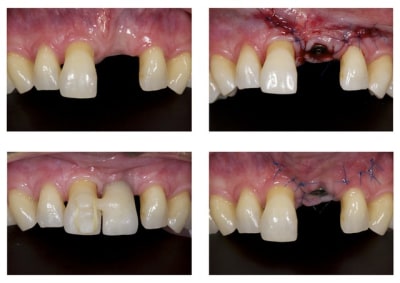

Merci jt2000, seespan et inset pour votre aide. Voici finalement le dispositif que l'on a choisi car je voulais me servir de l'implant comme ancrage.

je vous montrerai l'evolution, favorable ou.... défavorable.

je suis a l'écoute des ortho pour leurs conseils et critiques...

A virskn - Eugenol

B c15bbz - Eugenol

C abqhrm - Eugenol

07/11/2013 à 13h07

Le cas est terminé mais je ferai la photo finale lors du prochain controle.

Sans titre   copie cnlkjz - Eugenol

Comme demandé en MP voici le contrôle 10 mois après la pose.

C'est acceptable je pense. Ce traitement a ses limite bien sûr mais peut être une indication voire une alternative dans certains cas spécifiques comme celui-ci.

Au passage, qui connait le nom que l'on donne à cette collerette de GA que l'on voit sur 13-12-11-22-23, j'ai oublié.

A omtjjz - Eugenol

1 zf3owi - Eugenol

Img 0812 mvp6i0 - Eugenol